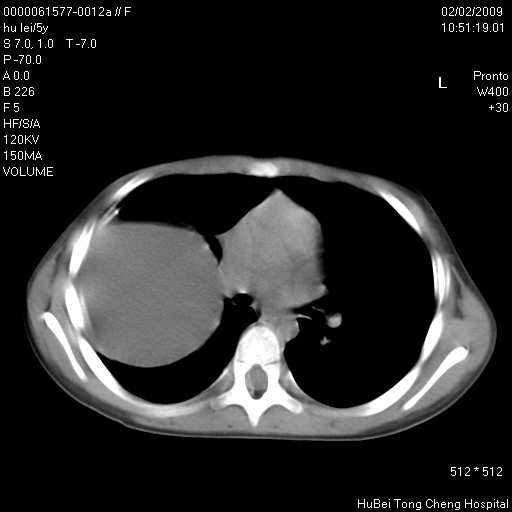

标题: PED1732:M5Y,右肺囊性占位!

患者:男,5。无明显不适,拍胸片考虑右肺囊肿。

行ct扫描,图象如下:

右肺巨大囊性占位性病变;考虑巨大肺囊肿,不排除淋巴管瘤可能。

病灶与前胸壁和右上纵隔、叶间裂界限不清,病灶前缘及内侧缘看不到正常的肺组织,不能排除包裹性积液。